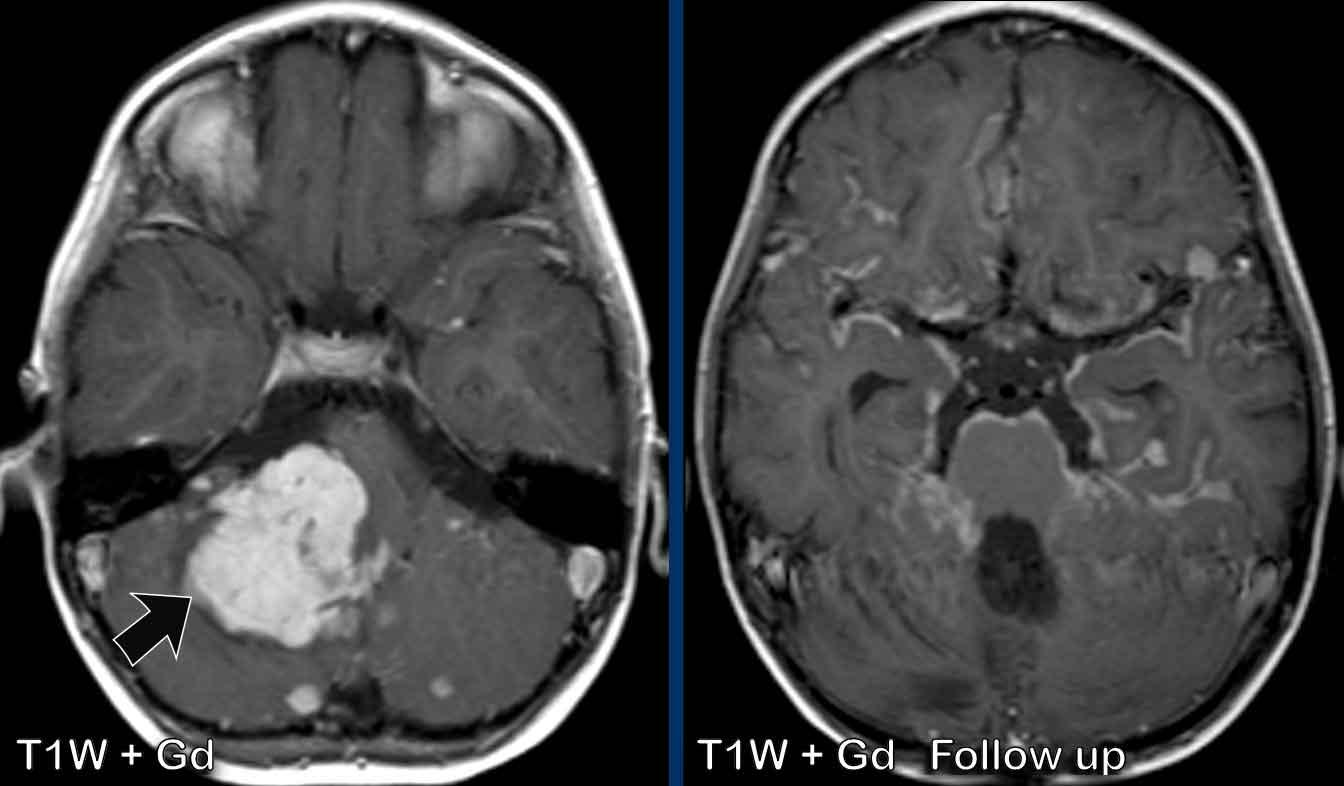

Đây là hình ảnh của một bé trai 9 tuổi được biết có u nguyên bào tủy hố sau.

Hình ảnh

U nguyên bào tủy biểu hiện là một khối ngấm thuốc lớn (mũi tên).

Có nhiều ổ ngấm thuốc nhỏ là dấu hiệu của di căn màng não mềm.

Tại lần theo dõi sau phẫu thuật và xạ trị, có ngấm thuốc màng não mềm dạng không đều và dạng nốt.

Kiểu ngấm thuốc “phủ đường” này được thể hiện rõ tại cầu não và lớp lót của các bể vallecular.